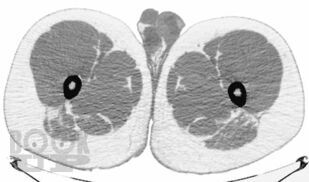

В руководстве подробно описана методология проведения компьютерно-томографического исследования при эндокринологических заболеваниях, рассмотрены основные диагностические аспекты и возможности компьютерной томографии при образованиях надпочечников, щитовидных и паращитовидных желез, гипофиза, заболеваниях костей и офтальмопатии. Продемонстрированы также возможности современной мультиспиральной компьютерной томографии в диагностике эндокринопатий. Издание иллюстрировано большим количеством компьютерных томограмм.